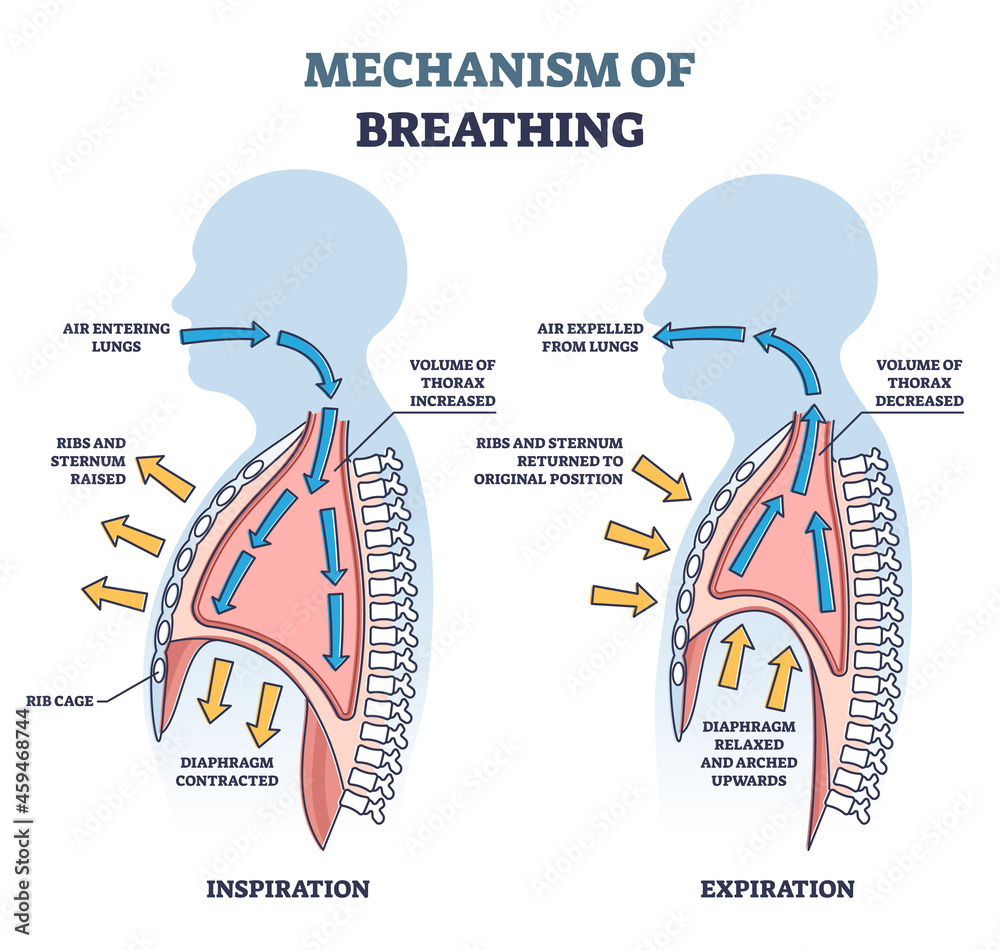

Normal Difference Between Chest Inspiration And Expiration

Normal Difference Between Chest Inspiration And Expiration

Mechanism Of Breathing As Anatomical Process Explanation Outline

Mechanism Of Breathing As Anatomical Process Explanation Outline

Normal Difference Between Chest Inspiration And Expiration - 2025 DIY